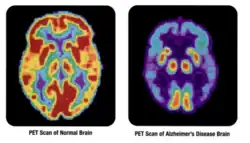

- 3D: ОФЭКТ — это трехмерный томографический метод, который использует данные гамма-камеры из многих проекций и может быть реконструирован в разных плоскостях. ПЭТ использует обнаружение совпадений для отображения функциональных процессов.

Проекция максимальной интенсивности (MIP) позитронно-эмиссионной томографии (ПЭТ) всего тела у женщины весом 79 кг после внутривенной инъекции 371 МБк 18F-FDG (за один час до измерения).

Нормальная ПЭТ/КТ всего тела с ФДГ-18. ПЭТ/КТ всего тела обычно используется для выявления, определения стадии и последующего наблюдения за различными видами рака. -

Аномальная ПЭТ/КТ всего тела с множественными метастазами рака. ПЭТ/КТ всего тела стала важным инструментом в оценке рака.